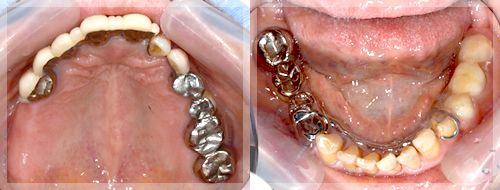

症例3. 抜歯を含めた総合的な咬合治療

| 術前 |

![]() |

年齢:73歳

主訴:全体的に見て欲しい。特に前歯がグラグラで見た目が悪い。

初診時の診断と治療方針

初診時の状態です。前歯の見た目が悪いのはもちろんですが、歯を損失してしまっているのに加え、ご自身の歯も歯周病に罹患しているため揺れてしまっており硬い物などはあまり噛めない状態です。つまり、審美面、咬合(噛み合わせ)、歯周病、齲蝕(虫歯)、適合の悪い被せものの治療が必要で抜歯を含めて総合的に治療をしていく必要性があります。